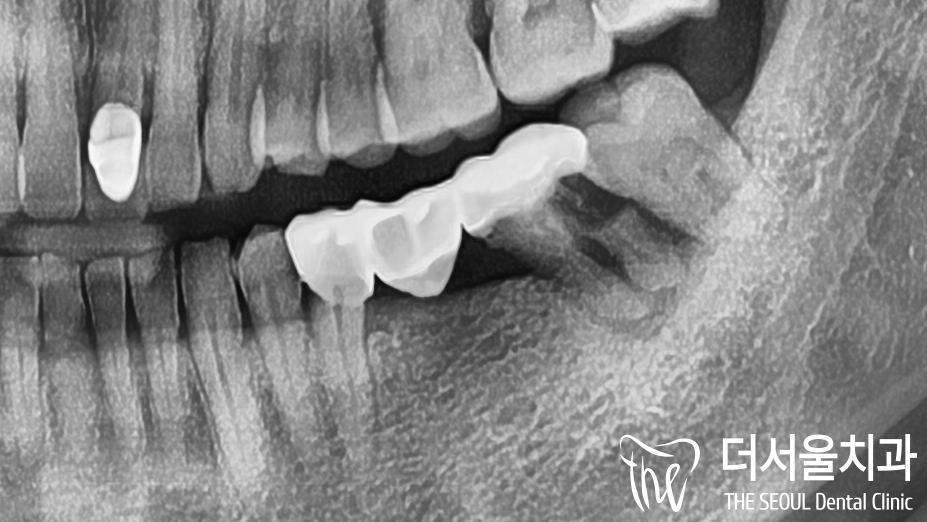

좌측 아래 어금니쪽을 보면 브릿지,

우측 어금니를 보면

켄틸레버 형태로 제작된 브릿지가 관찰됩니다.

*켄틸레버 : 한쪽만 고정이 되어있는 형태

좌측이 원인이란 생각이 들었는데요.

자세히 살펴보니 지대치 치근 부위로

심한 손상이 나타나 있었습니다.

육안으로 관찰했을 때에는 보철이 씌워져 있어

별다른 문제를 발견하지 못했지만,

잇몸 쪽을 자세히 살펴보면

울긋불긋하게 염증이 생겨있음을 알 수 있습니다.

치아에 문제가 생겼다면

잇몸에도 자연스레 이상이 생기게 되는거죠.